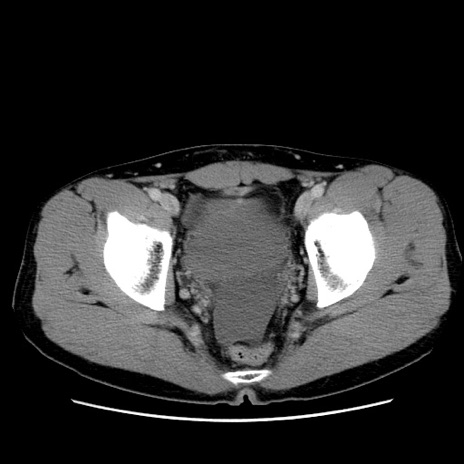

冠状断像

【症例】20歳代 男性

【主訴】心窩部痛

【現病歴】今朝より上腹部痛あり。一旦軽快していたが再度出現したため救急要請。昨日夕に白身の魚を含む刺身を食べた。

【身体所見】BP 136/89mmHg、HR 74/min、BT 37.0℃、腹部:膨満、軟、心窩部に圧痛あり。反跳痛なし、筋性防御なし、腸雑音やや亢進あり。

【データ】WBC 17700、CRP 0.48